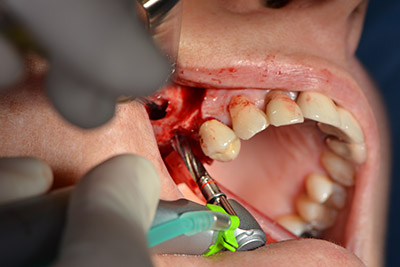

Следващата стъпка е синус лифт с непосредствено имплантиране. Implantmed е предварително настроен на първа позиция за букална фенестрация на стената на максиларния синус.

Фенестрацията е извършена при 35,000 rpm и след това носната лигавица е обработена по посока на челюстта (Фиг. 13 to 14).

Имплантът е поставен и костта е изградена. В този случай, поради големината на зоната за аугментация, автогенните костни парченца, събрани с костен сондаж след имплантирането в зона 16 и фенестрацията в зона 14, са смесени с костозаместващ материал.